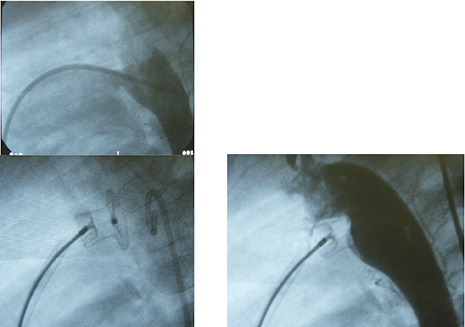

PDA closure using ADO at that time.